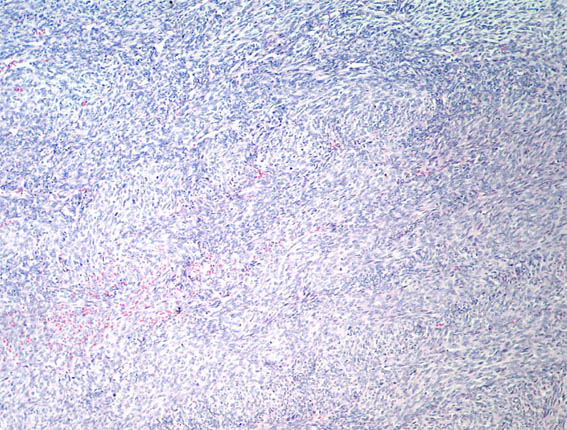

Figure 3. H&E, X100.